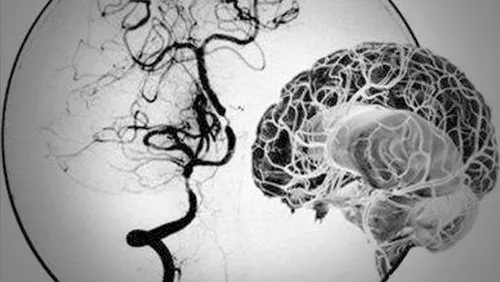

:“烟雾病是因为大脑主要动脉出现狭窄或堵塞,导致大脑供血不足,大家都知道人的大脑缺血是很严重,那这个时候怎么办呢?其实我们身体早就感觉到有问题了,它就想着:既然那条主要大血管不行那就小血管上,这个时候那些小血管听到指令就会扩张,给大脑供应更多的血液。而这些异常扩张的小血管网在脑血管造影图像上很像烟雾,所以被称为【烟雾病】。”